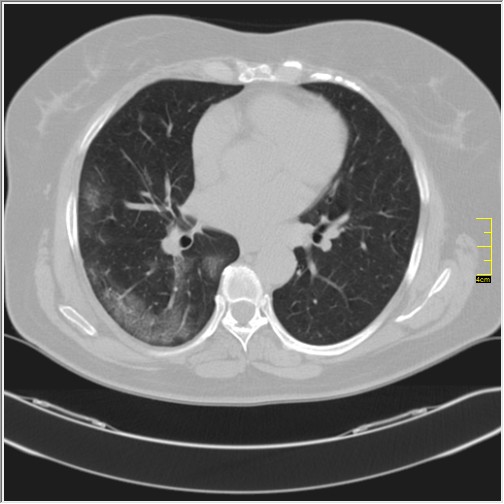

Da ne poredim više sa divljim sojem, omikron se ponaša prilično profilisano, ako je to najadekvatniji izraz koji se može primeniti. Pravi fibrozu kao delta soj, skoro odmah. Osnovna razlika je u izgledu ground glass promena i njihovoj distribuciji.

Možemo da zapazimo pravilnosti u slici, nema dominantno bazalne distribucije, ravnomerno se razvija u svim delovima pluća ali ipak blisko uz pleuru. To ga čini teško vidljivim na rdg snimcima. Fibroza ide odmah. Limfni nodusi nisu uvećani kao kod alfa soja, krvni sudovi reaguju samo u zahvaćenim područjima, kod dosadašnjih, posebno alfa i delta, reagovali su svuda.

Ono što je karakteristično je to da su ovo nalazi koji su 2. i 3. dana bolesti u I fazi. Znači ne u progresivnoj, već u uvodnoj fazi kada uglavnom nema CT znaka. Fibrozne trake već drugog dana. Ground glass oko većih grana bronha. Kao da bolest ne može da sačeka, kao da klija gde stigne.